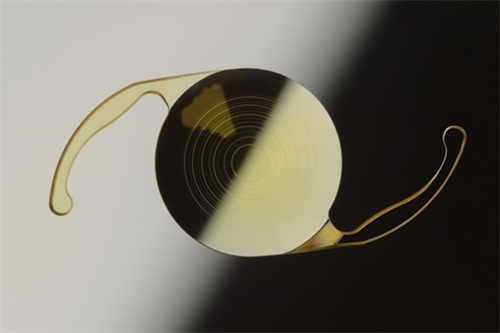

进口人工晶体常采用疏水性丙烯酸酯、硅胶等高端材料。

这些材料不仅生物相容性更优,还能降低后囊混浊风险,延长晶体使用寿命。

近年来,国产晶体在材料研发上进步显著。爱博诺德的非球面人工晶体采用国产疏水性丙烯酸酯,通过优化表面处理工艺,有效减少球差,成像质量已接近进口同类产品;天仁的折叠式晶体则以“超薄设计”为亮点,植入时切口更小,术后修养更快。

部分国产高端晶体甚至开始尝试“抗沉积涂层”技术,进一步降低术后炎症反应。